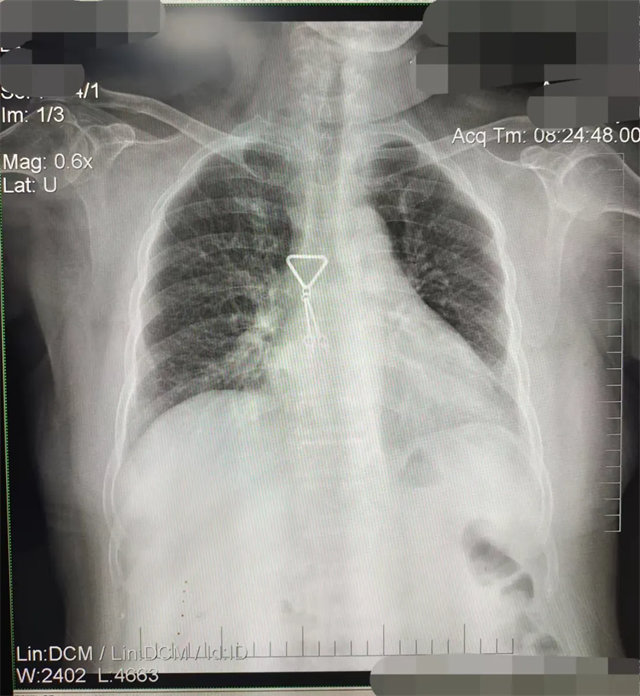

缺陷:肩胛骨未完全拉離肺野,吸氣不完全,存在金屬偽影遮擋,略有聳肩,且肺尖顯示不好,圖像顆粒感較強(qiáng),管電流量不夠,信噪比偏低。

解決:去除金屬物品后,按標(biāo)準(zhǔn)體位,使患者雙肩旋前與前胸一并緊貼成像件,適當(dāng)調(diào)高mAs,然后深吸氣后屏氣曝光。